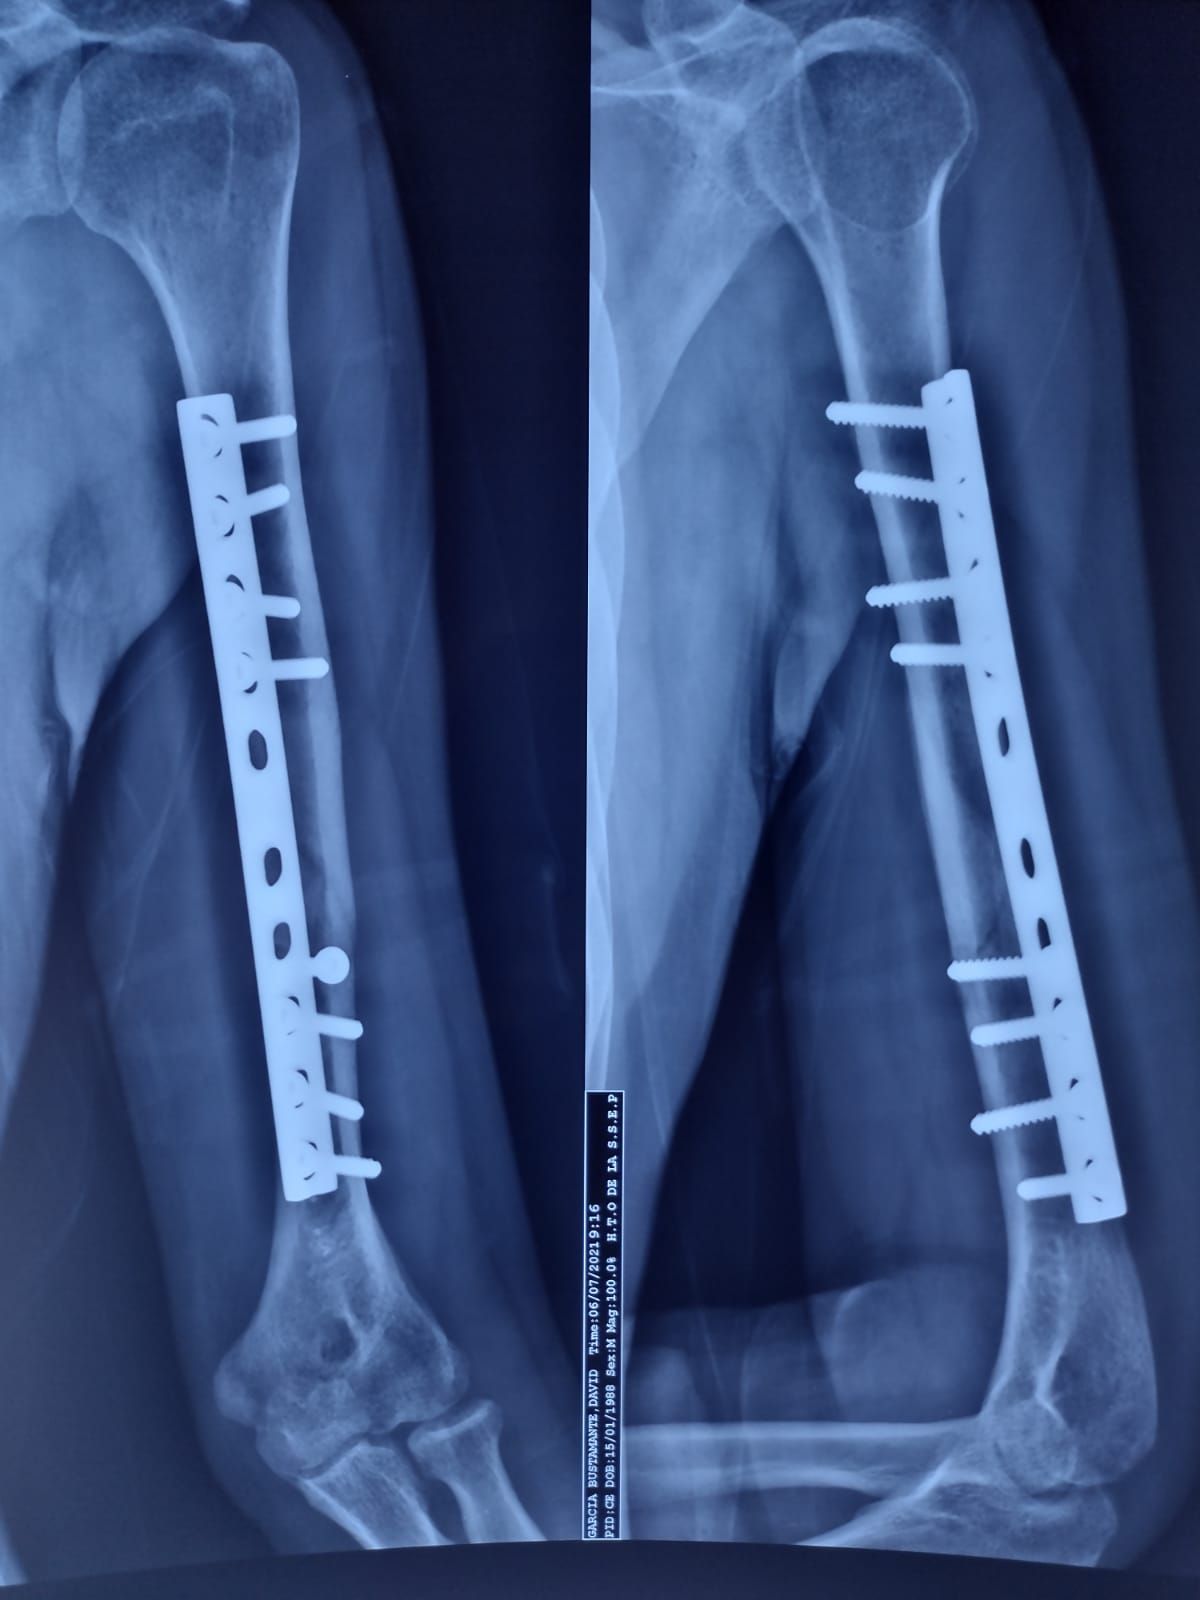

Reparación fractura de húmero Sin especificar